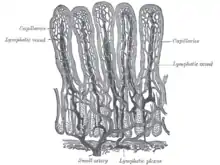

The surface for absorption is increased in many ways: the mucosa of the small intestine is thrown into folds called rugae; the mucosa itself has numerous finger-like projections called villi, and the epithelial cells are also covered with numerous projections called microvilli. The microvilli give the appearance of a 'brush' on light microscopy; hence the term brush border. The following illustration shows the anatomy of a villi:

Mucous is secreted by numerous goblet cells; other cells are specialized for absorption and are known as absorptive cells. In the base of the crypts are numerous secretory cells which secrete the digestive enzymes of the small intestine. Some of the crypts penetrate into the submucosal layer, forming digestive glands which will communicate with the mucosa via a secretory duct.

Epithelial cells have a lifetime of 5–7 days. New cells are continuously being generated in the crypts, and migrate up the sides of the villi. These cells differentiate into either goblet cells (10–25%) or absorptive cells. Old cells are shed from the tips of the villi, migrating upwards and forming new villi.